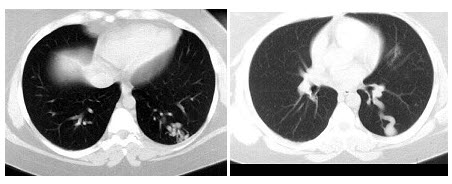

C.肌肉梗死

男,58岁,头痛、恶心、行走不稳,肺和脑CT检查如图,最可能的诊断为()

A.星形细胞瘤